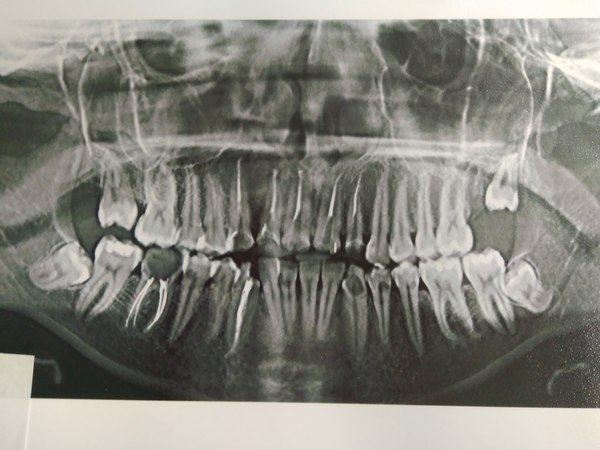

Ах да, кто интересовался фотографиями: их нет :( Ну в смысле фото "до" я не делала никогда (для меня это была не самая приятная тема), когда началось лечение мне вообще было не до того и я откровенно забыла, что есть люди интересующиеся этим. "После" делать тоже смысла нет- не самый светлый цвет, но вполне здоровый, зубы как родные, смотреть в общем не интересно, если не с чем сравнить. Было фото "забора" разве что, но туда жесть нужна явно, да и найти не могу чего-то. Еще есть снимок до установки штифтов, в середине лечения и переделки работы криворуких мудаков что занимались мной раньше. Качество какое есть, пардоньте :( Комментарии от врачей о состоянии моих зубов были в прошлом посте. Оказалось не так все дерьмово как выглядит.